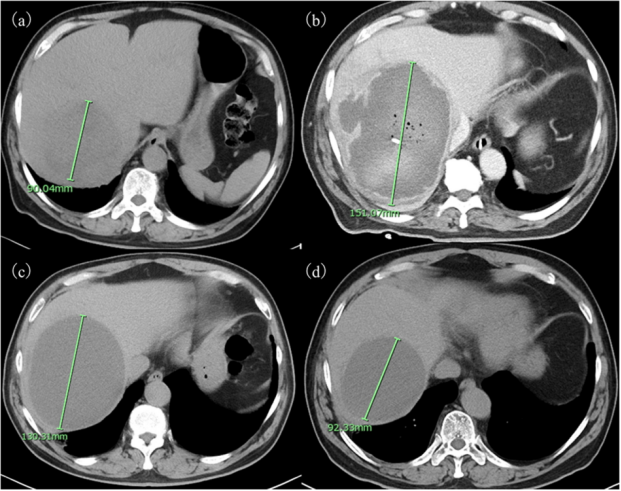

- 中年女性无症状肝脏多发病灶,原因为何? 医脉通-临床病例平台患者女,45岁,因影像学检查偶然发现肝脏多发病灶就诊。患者无相关症状,体格检查正常。……